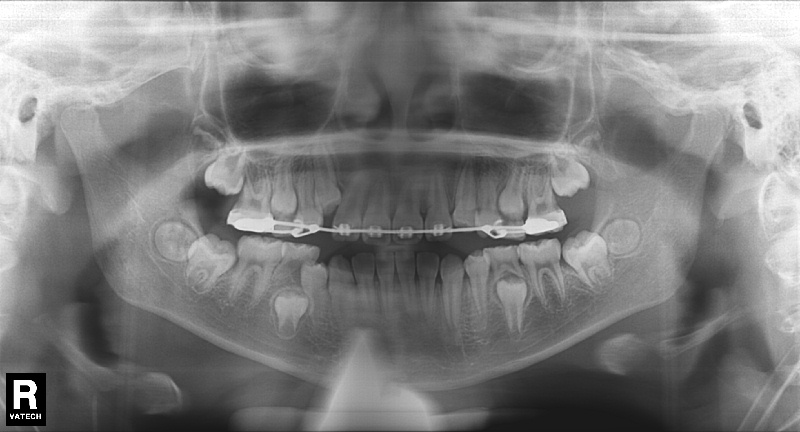

치료 후 사진입니다.